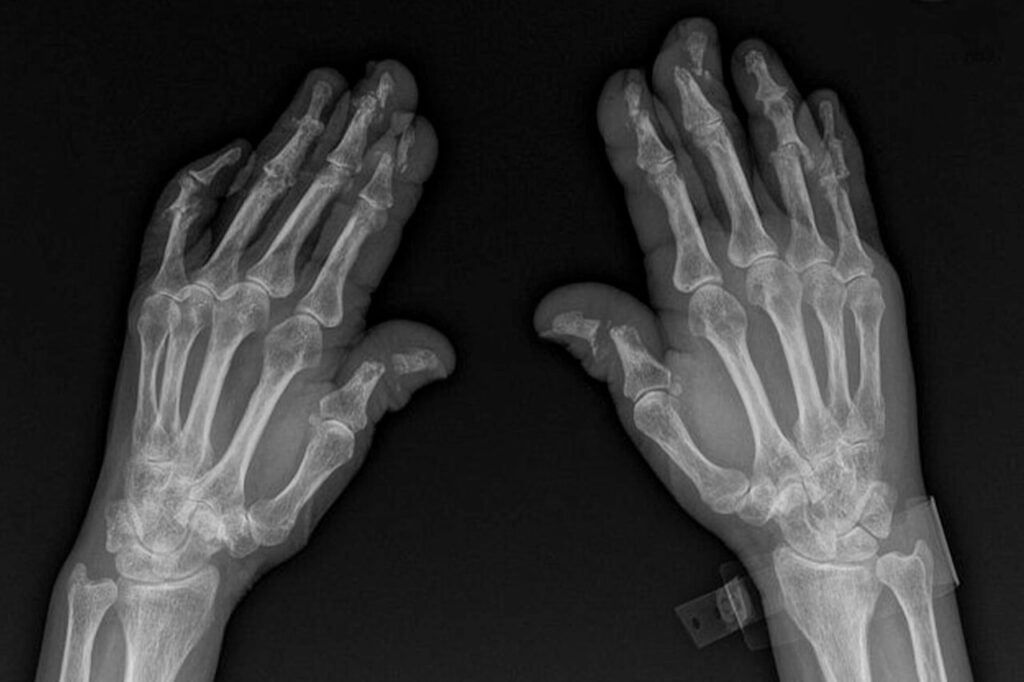

Pencil-in-cup deformitet er en usædvanlig og alvorlig misdannelse af fingerleddene, som kan opstå ved meget aggressiv eller ubehandlet psoriasisgigt i hænderne. Navnet beskriver præcist, hvordan leddet ser ud på et røntgenbillede. Ved denne tilstand eroderer toppen af en mellemhåndsknogle (metacarpal) så meget, at den bliver tynd og spids som en blyant. Samtidig eroderer bunden af den overliggende fingerknogle i midten, mens den vokser i kanterne, hvilket skaber en hulning, der ligner en kop. Resultatet er et billede, der ligner en blyant, der er placeret i en kop. Dette er en unik manifestation af psoriasisgigt, fordi sygdommen både forårsager knogledestruktion (erosion) og ny knogledannelse (proliferation) i det samme led.

Diagnosen kan ikke stilles ved en almindelig fysisk undersøgelse alene. Selvom en læge kan have mistanke baseret på symptomer som en forkortet finger, er den endelige diagnose radiologisk. Det betyder, at den kun kan bekræftes via et røntgenbillede, som tydeligt viser den karakteristiske blyant- og kopformede erosion af knoglerne.